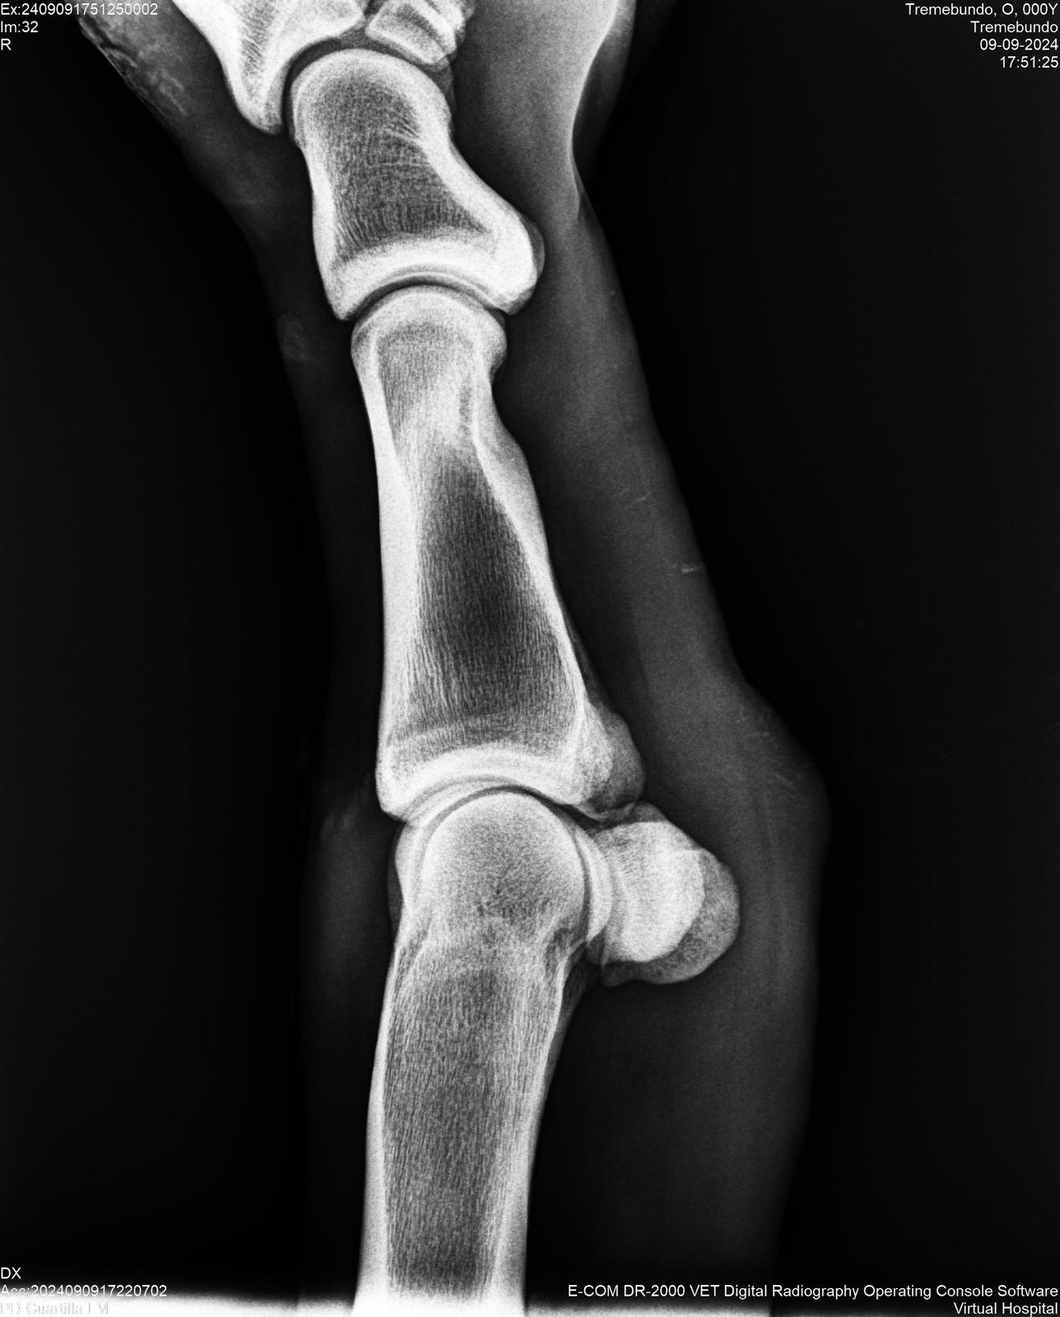

LOTE 37, TREMEBUNDO

Identificador: #291140-

Generacion 2022